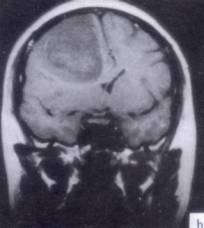

问题 病历摘要:??患者男性,52岁。头痛伴呕吐2月,呕吐呈喷射性。既往身体健康。体检:神清,表情淡漠,反应迟钝,双眼底视神经乳头明显水肿,左鼻唇沟稍浅,左腹壁反射减弱,左上下肢肌力4级,左Babinski征(-)。 下列关于多形性胶质母细胞瘤的叙述哪些是正确的?提示:肿瘤病理报告为多形性胶质母细胞瘤